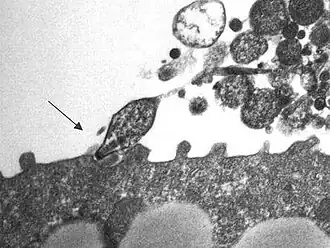

Mycoplasma pneumoniae ist ein zellwandloses Bakterium und im Vergleich zu anderen Bakterien sehr klein (ca. 10 % des Volumens von Escherichia coli). Im Gegensatz zu anderen Bakterien kann es Cholesterin nicht selbst produzieren, sondern muss es aus der Umgebung aufnehmen. Der Keim besitzt ein besonderes Organell, mit dem er sich an das Flimmerepithel des Respirationstraktes anheften kann.[1] Weitere Pathogenitätsfaktoren sind Superantigene und die Produktion von Wasserstoffperoxid (H2O2).[2]